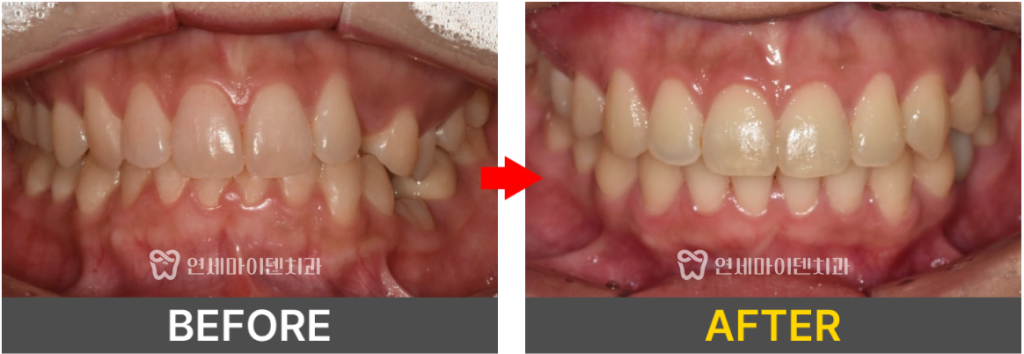

정면 구내 사진을 보면 왼쪽 위 송곳니가 보이지 않았고,

왼쪽 아래에는 유치가 남아 있는 상태였습니다.

치료 시작 약 1년 4개월 후,

바깥으로 돌출되었던 어금니와

안쪽으로 매복되어 있던 송곳니가

모두 제자리를 찾아 배열되었습니다.

위아래 중심선도 잘 맞춰졌고,

전체적으로 치열이 가지런하게 정돈된 모습을 확인할 수 있었습니다.

최종적으로 안쪽에 숨어있던 송곳니가 정상 배열을 이루고,

유치 부위에는 임플란트가 정확히 식립되어

기능적·심미적으로 모두 회복되었습니다.

비정상적으로 물리던 가위교합도 개선되었고,

중심선이 맞지 않았던 부분도

교정 후 확실히 균형을 되찾았습니다.

처음에는 비대칭이 심했던 교합이

이상적인 형태로 완성되었습니다.